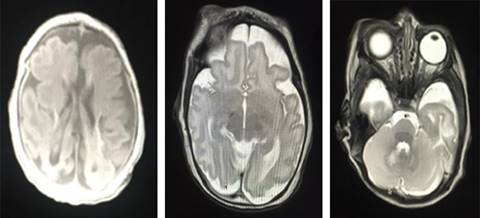

Estudios de imagen. En el USG transfontanelar se reportó: imágenes hiperecoicas compatibles con probables calcificaciones. La tomografía de cráneo: atrofia cortical y subcortical, calcificaciones parenquimatosas. Imagen de resonancia magnética: disgenesia de cuerpo calloso, paquigiria, calcificaciones subcorticales y periventriculares, disminución de volumen cortico-subcortical (Figuras 1 y 2).

Figura 1: Resonancia magnética nuclear: atrofia cortical y subcortical, calcificaciones parenquimatosas.